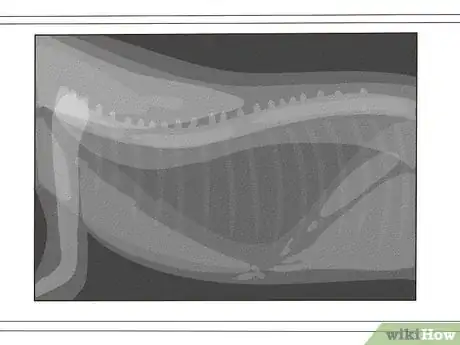

If your cat has suddenly started wheezing or breathing loudly, you may be wondering if they have feline asthma—a respiratory condition that causes inflammation and spasms in the lungs. While this can understandably be upsetting, rest assured that taking your cat to the vet and getting treatment will dramatically help. Even if your cat does have asthma, it is extremely manageable and there’s no reason your cat can’t live a healthy, full life. In this article, we’ll walk you through everything you need to know about treating a cat with asthma.

- ↑ https://tvmdl.tamu.edu/2019/06/24/cat-diagnosed-with-feline-asthma/